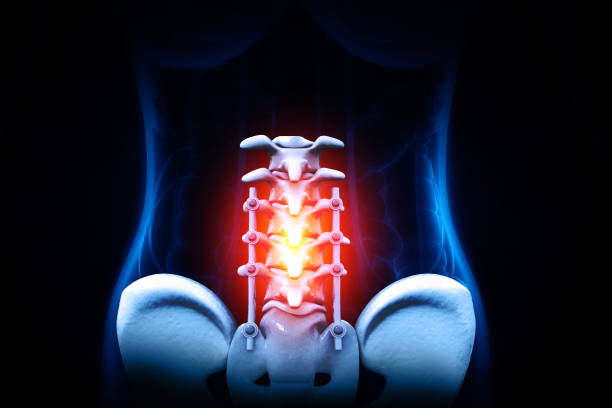

척추관협착증에 대한 이해

척추관협착증은 척추 주변의 근육과 인대가 퇴행하여 척추관 내 황색 인대가 비정상적으로 부풀어 오르면서 발생하는 퇴행성 척추질환 중 하나입니다. 이 질환은 가까운 거리도 통증으로 인해 걷기가 어려워지는 특징을 가지고 있으며, 새벽에 다리에 통증을 느끼는 경우가 많습니다.

척추관협착증은 다른 척추 질환에 비해 퇴계 정도가 매우 심한 질환으로, 퇴행이 심할수록 근육과 인대가 더욱 뭉쳐지고 더 많은 압력을 가하게 됩니다. 이 때문에 근육과 인대를 풀어주는 것이 중요하며, 이를 위한 가장 적합한 운동이 걷기입니다.